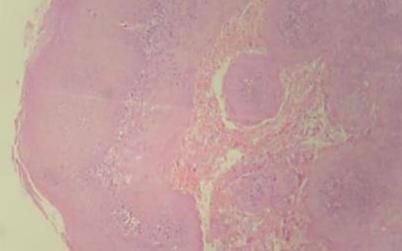

Se tomó biopsia incisional donde se observóepitelioescamosoestratificadoque se continua con masas células neoplásica conpleomorfismocelularynuclear,pérdida de la relación núcleo citoplasma, mitosis aberrantes y aumentadas, nucleolos evidentes y queratinización individual y grupal que infiltraban tejido conjuntivo subyacente; (Fig. 12) por lo que se diagnósticacomoCarcinomaoraldecélulas escamosas, Se realizo PCR al bloque de parafinapor indicación deloncólogodonde fuepositivoalVPH52,porloqueseindicó inmunoterapianeoadyuvante

Fig. 12

Carcinoma oral de células escamosas, vista microscópica, tinción hematoxilina y eosina, autoría propia.

Nota:Fototomadaporelautor